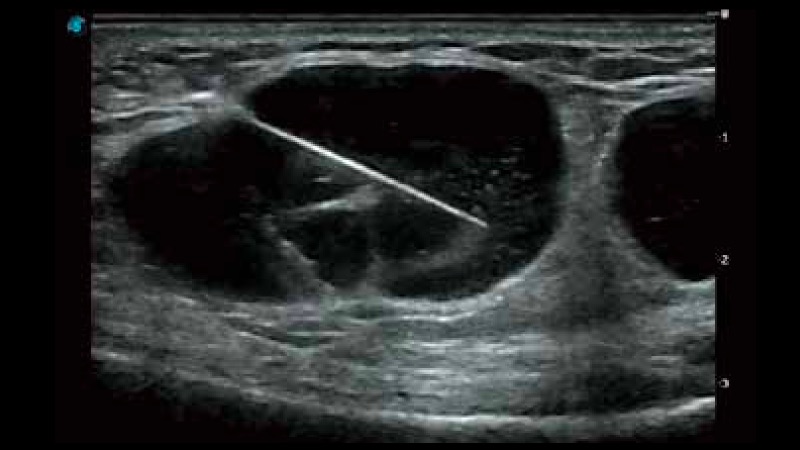

開立醫(yī)療通過不斷的技術(shù)創(chuàng)新,為大眾的生命健康提供持續(xù)關(guān)愛。P12 Plus采用全新一代超聲成像平臺,新平臺旨在將真實還原組織解剖結(jié)構(gòu)作為首要目標(biāo)。平臺采用全新集成化硬件模塊,搭載新一代芯片,系統(tǒng)性能得到大幅提升,為您的診斷提供了豐富的臨床信息。優(yōu)異的圖像表現(xiàn),豐富的探頭配置,全面的應(yīng)用功能,為您日常診斷提供了可靠的助手。

彩色多普勒超聲診斷系統(tǒng)